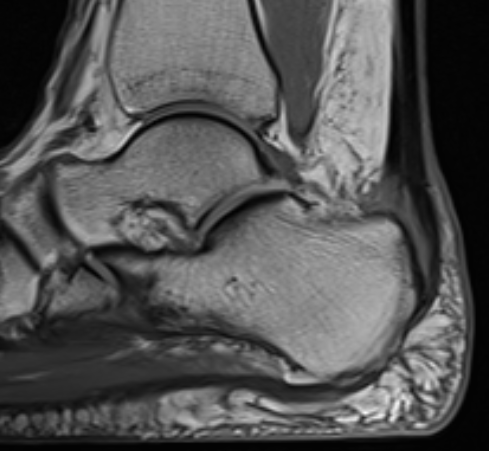

Retrocalcaneal bursitis with Haglund's

Partial tearing at insertion with retrocalcaneal bursa

Tendon thickening, Haglund's deformity and retrocalcaneal bursa

MRI grading

- Grade I: 6 - 8 mm thickening

- Grade II: > 8 mm tendon thickness with < 50% tendon degeneration

- Grade III: > 8 mm tendon thickness with > 50% tendon degeneration